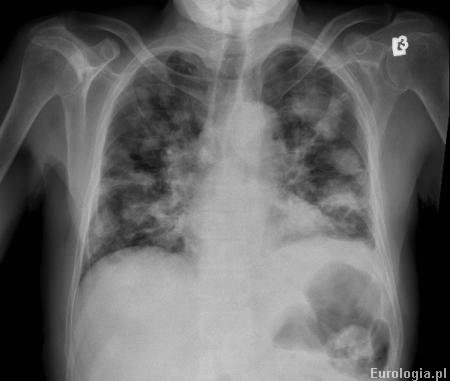

Rak rdzeniasty nerki - łac. Renal medullary carcinoma jest agresywną postacią raka nerki. Rak rdzeniasty nerki jest bardzo rzadkim nowotworem, który najczęściej atakuje osoby młode. Według literatury większość pacjentów z rakiem rdzeniastym nerki miało współistniejącą niedokrwistość sierpowatokrwinkową. U większości pacjentów z tym typem raka nerki w momencie rozpoznania stwierdza się przerzuty uogólnione. W przypadku przerzutów odległych rokowanie jest niekorzystne dla pacjenta.

Fot. Przerzuty do płuc u pacjenta z rakiem nerki.